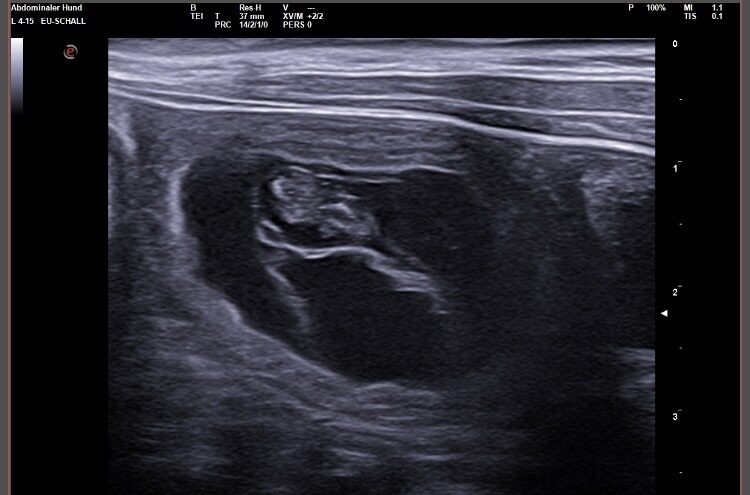

Wir waren erfolgreich und konnten Fruchtanlagen mit schlagenden Herzen sehen. Wir gehen zum aktuellen Zeitpunkt wieder von einem größeren Wurf aus. Daykos und Dorias Rendevouz war also sehr vielversprechend!

Hier zeigen wir euch einige der kleinen gefüllten Fruchtblasen mit Inhalt und schlagenden Herzen. Da wir kurz vor Ostern mit der Geburt rechnen, nennen wir sie „Ostereier“ 🙂